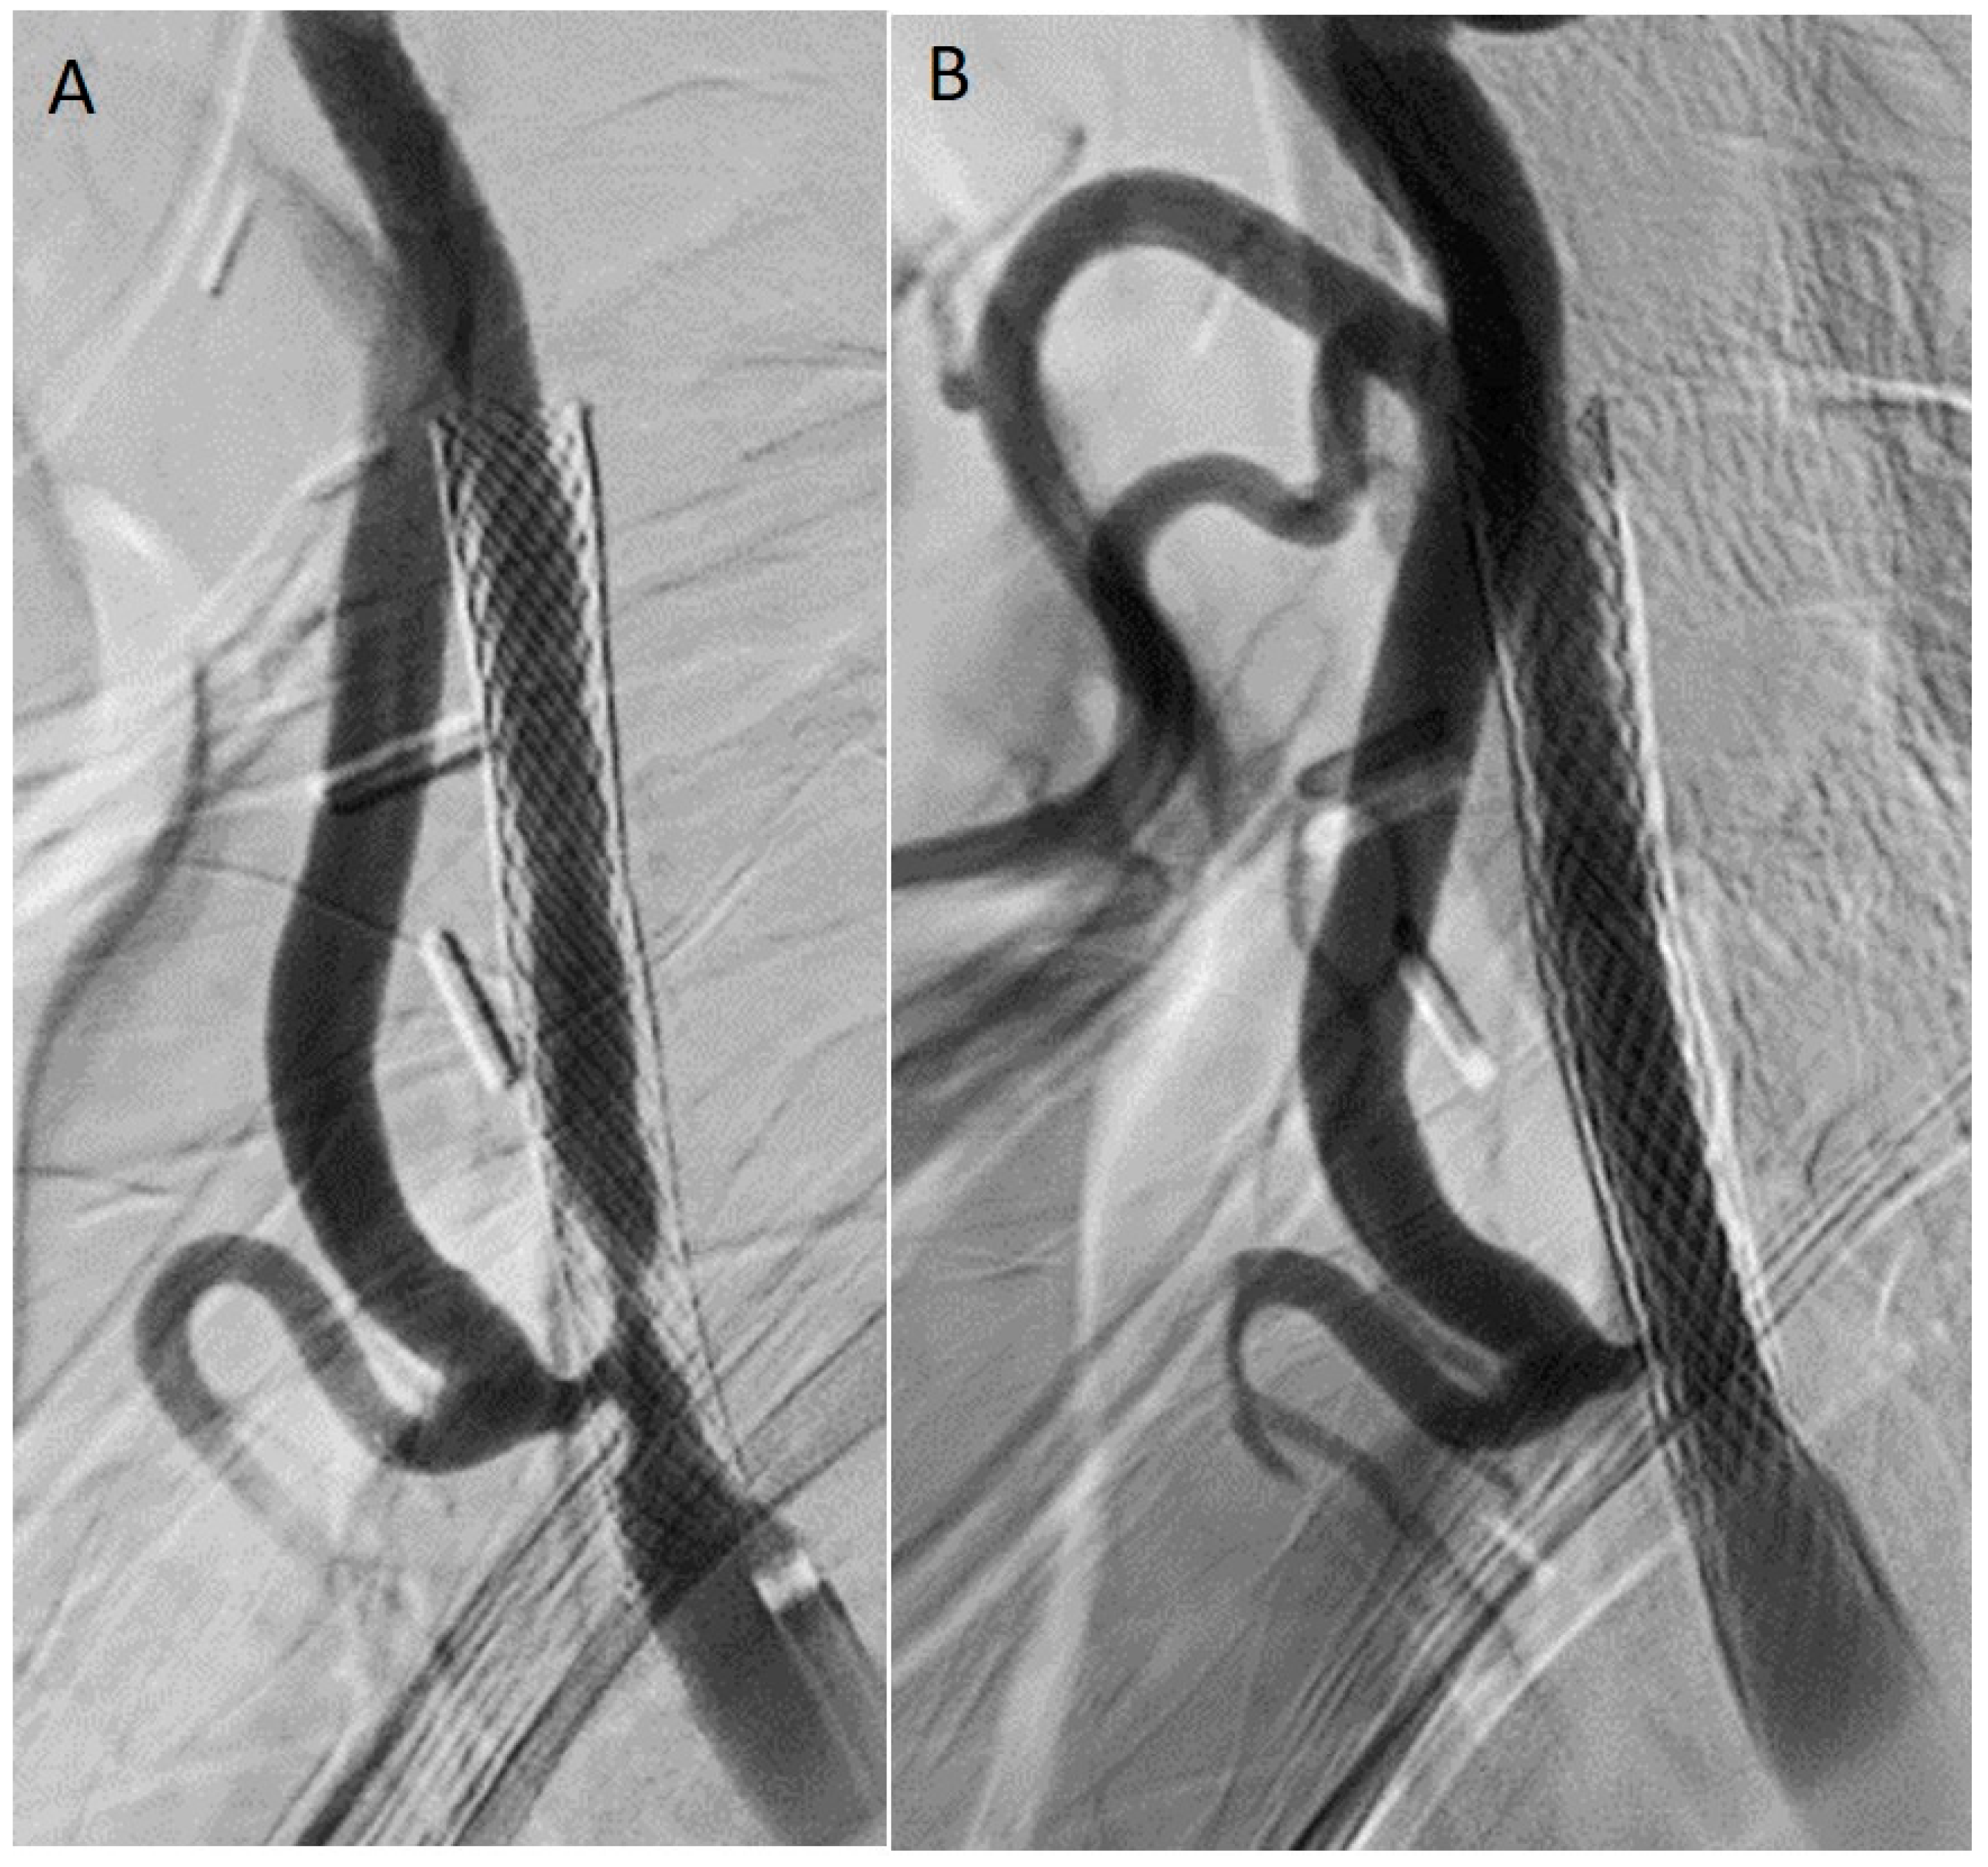

8.2.3. Drug-Coated Balloon (DCB) Angioplasty